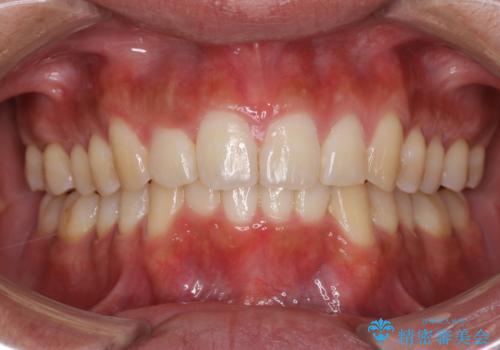

インビザラインによる出っ歯の矯正

- 出っ歯と下の歯のガタガタを主訴に来院されました。

上の奥歯を後方に移動させて、スペースを作り前歯を内側に引っ込める計画としました。

インビザラインによるマウスピース矯正で治療をすることとしました。

インビザラインをしっかり使用していただいたので、スムーズに治療をおえることができました。